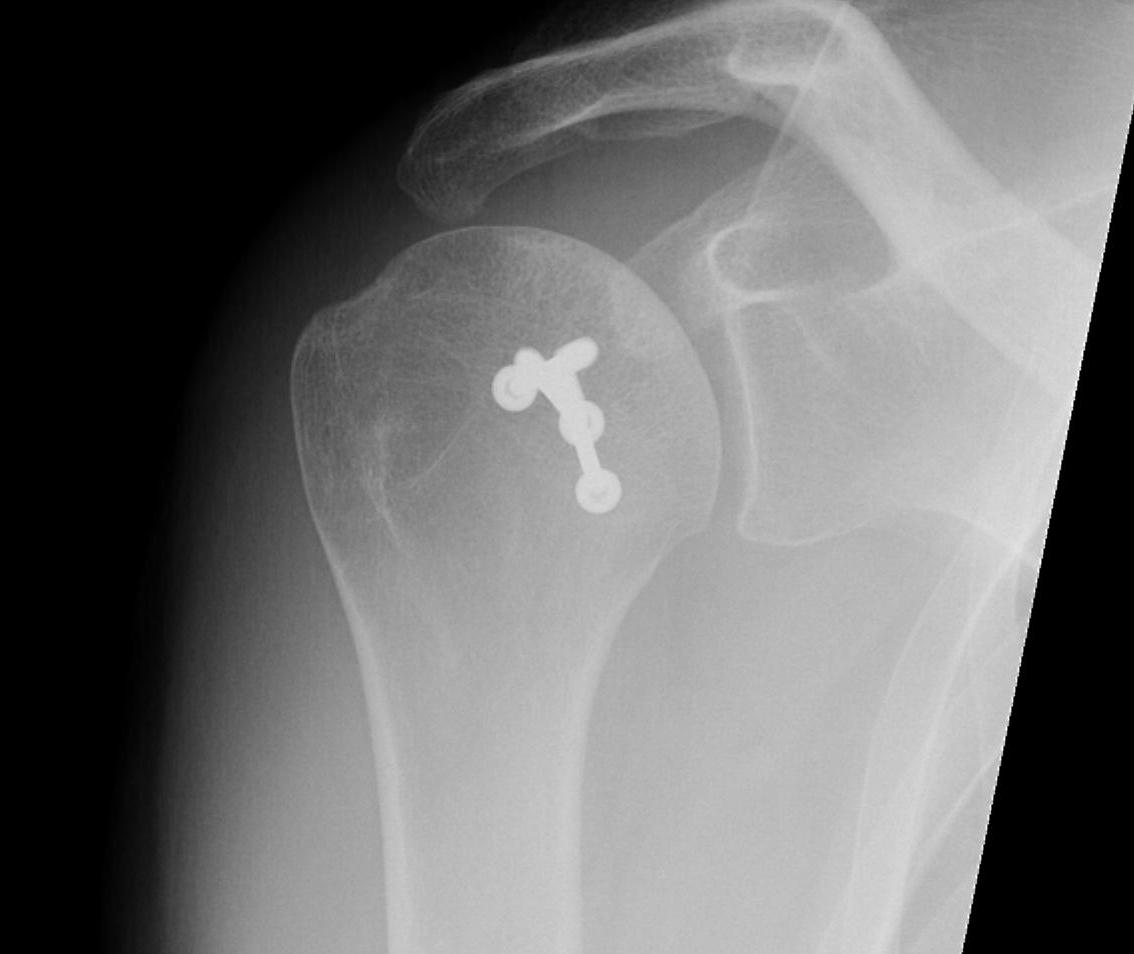

Subscapularis +/- Lesser tuberosity transfers

Indications

Defects 25%

Options

McLaughlin - subscapularis transfer into defect / makes defect extra-articular

Neer modification - lesser tuberosity + subscapularis transfer into defect

Results

- systematic review of modified McLauglin for locked posterior dislocation

- 9 studies and 97 shoulders

- reverse Hill Sachs 20 - 50%

- 100% union

- complication 1% (screw loosening)

- recurrent instability 2% (epileptic patients)